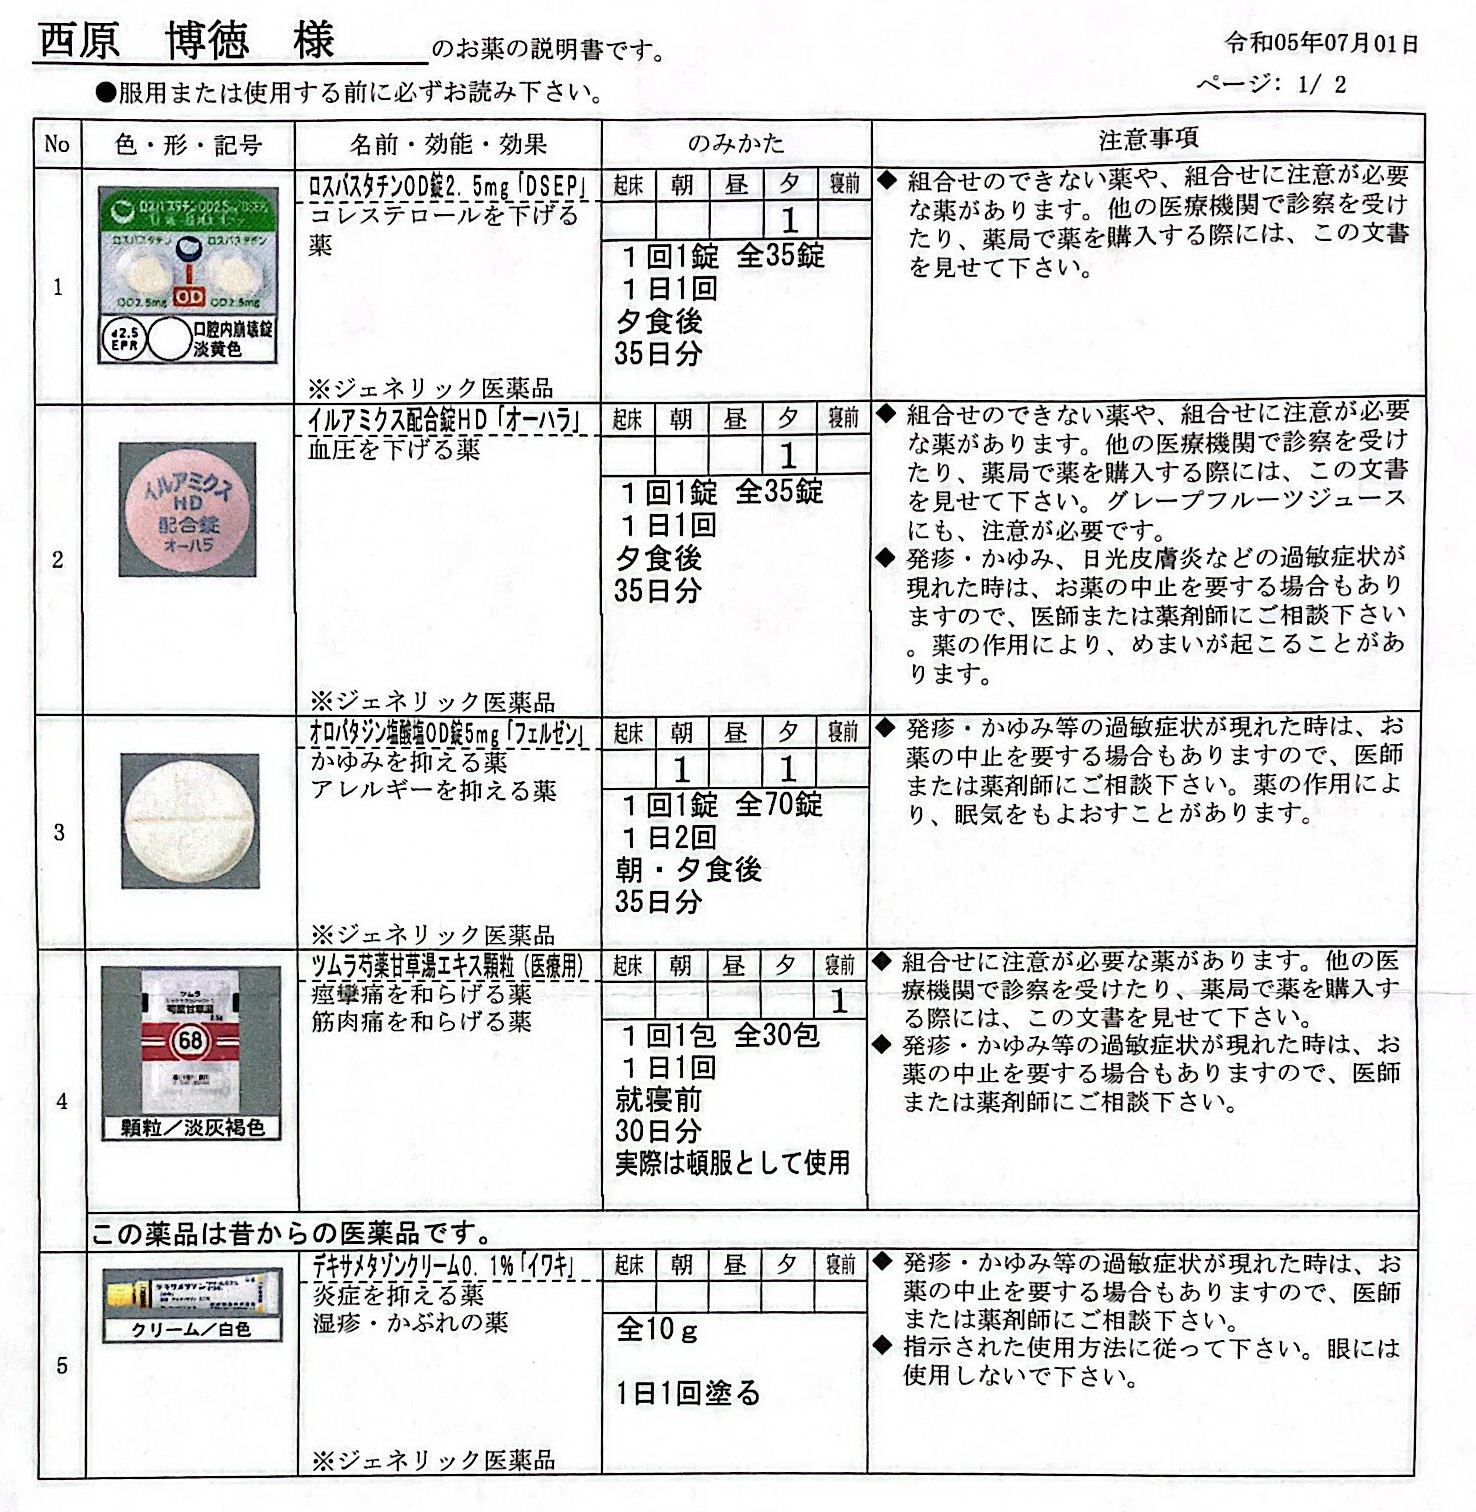

2025.1.31 江崎耳鼻咽喉科

レボセチリジン塩酸塩錠5mg「武田テバ」 モンテルカスト錠10mg「トーワ」

2024.12.7 西原クリニック定番薬 (リンデロンはベタメタゾンに変更:同等)

22.10.29 鼻炎薬吸引 モメタゾン点鼻液50μg 噴霧用 5mg10g 杏林 56噴霧用

62:防風通聖散=膨満感対応 68:芍薬甘草湯=こむら返り対策

2024.3.9 点眼薬 アレジオン